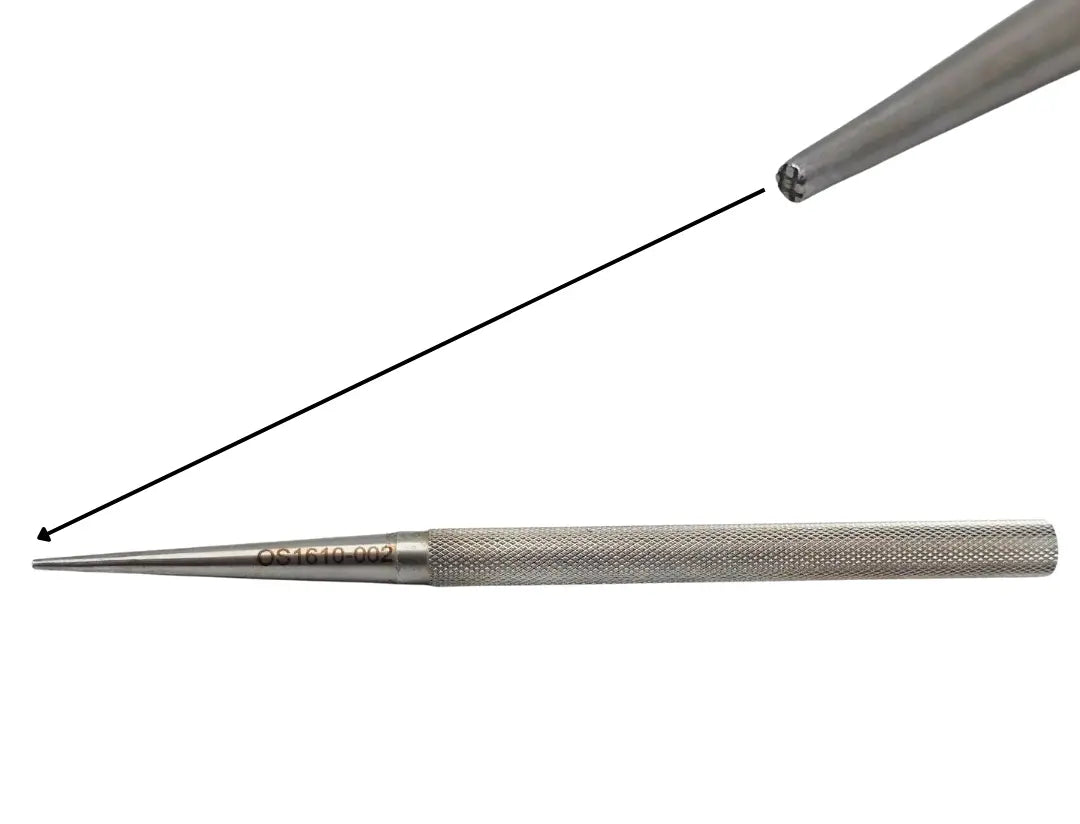

V. Mueller OS1610-002 Bone Tamp 2 mm Cross Serrated Tip 6.25 in

V. Mueller OS1610-002 Bone Tamp 2 mm Cross Serrated Tip 6.25 in

• Model: OS1610-002

• Overall Length: 6"

The V. Mueller OS1610-002 is a bone tamp with a 2 mm cross-serrated tip, measuring approximately 6¼ inches in overall length. The serrated tip is designed to grip and compact bone material during orthopedic procedures, aiding in precise manipulation and stabilization. The model number “OS1610-002” is engraved for positive identification.

Crafted from surgical-grade stainless steel, this tamp offers durability and resistance to corrosion under repeated use and sterilization. Its shaft is straight and rigid, providing controlled force transmission, while the serrated end maintains grip even in slippery or irregular bone surfaces.

This instrument is suited for orthopedic or general surgery sets that require fine tamping tools. Its design makes it useful for small bone work, compacting grafts, or preparing bone beds in reconstructive procedures where accuracy and control are critical.